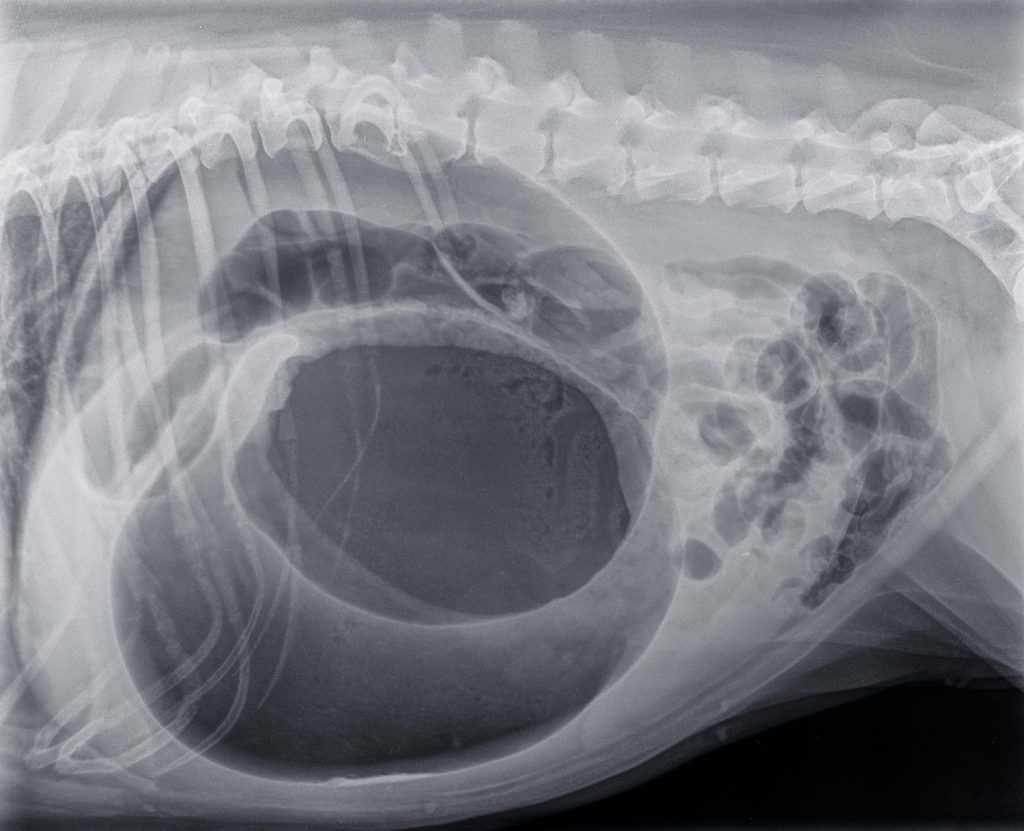

Bij een typisch beeld van de hiervoor genoemd signalement en verschijnselen, kan de diagnose vaak snel gesteld worden. Bij ernstige twijfel kunnen röntgenfoto’s van de buik gemaakt worden, dit geeft echter wel vertraging in de behandeling.